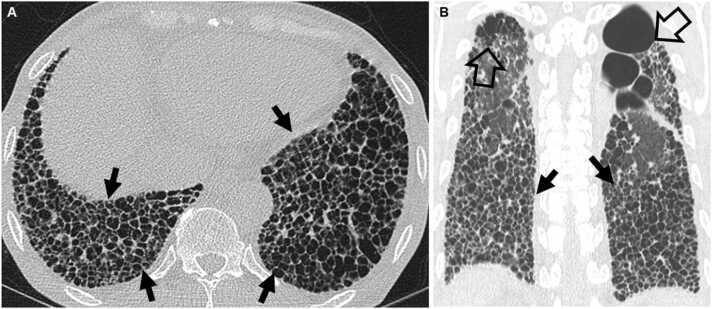

Connective tissue diseases (CTDs) demonstrating features of interstitial lung disease (ILD) include systemic lupus erythematosus (SLE), rheumatoid arthritis (RA), systemic sclerosis (SSc), dermatomyositis (DM) and polymyositis (PM), ankylosing spondylitis (AS), Sjogren syndrome (SS), and mixed connective tissue disease (MCTD). On histopathology of lung biopsy in CTD-related ILDs (CTD-ILDs), multi-compartment involvement is an important clue, and when present, should bring CTD to the top of the list of etiologic differential diagnoses. Diverse histologic patterns including nonspecific interstitial pneumonia (NSIP), usual interstitial pneumonia (UIP), organizing pneumonia, apical fibrosis, diffuse alveolar damage, and lymphoid interstitial pneumonia can be seen on histology in patients with CTD-ILDs. Although proportions of ILDs vary, the NSIP pattern accounts for a large proportion, especially in SSc, DM and/or PM and MCTD, followed by the UIP pattern. In RA patients, interstitial lung abnormality (ILA) is reported to occur in approximately 20-60% of individuals of which 35-45% will have progression of the CT abnormality. Subpleural distribution and greater baseline ILA involvement are risk factors associated with disease progression. Asymptomatic CTD-ILDs or ILA patients with normal lung function and without evidence of disease progression can be followed without treatment. Immunosuppressive or antifibrotic agents for symptomatic and/or fibrosing CTD-ILDs can be used in patients who require treatment.

表现为间质性肺疾病(ILD)特征的结缔组织病(CTD)包括系统性红斑狼疮(SLE)、类风湿关节炎(RA)、系统性硬化症(SSc)、皮肌炎(DM)和多发性肌炎(PM)、强直性脊柱炎(AS)、干燥综合征(SS)以及混合性结缔组织病(MCTD)。在CTD相关ILD(CTD-ILD)的肺活检组织病理学检查中,多部位受累是一个重要线索,若出现这种情况,应将CTD列为病因鉴别诊断的首要考虑。CTD-ILD患者的组织学检查可见多种组织学模式,包括非特异性间质性肺炎(NSIP)、寻常型间质性肺炎(UIP)、机化性肺炎、肺尖纤维化、弥漫性肺泡损伤和淋巴细胞间质性肺炎。尽管ILD的比例各不相同,但NSIP模式占很大比例,尤其是在SSc、DM和/或PM以及MCTD中,其次是UIP模式。据报道,RA患者中约20%-60%会出现间质性肺异常(ILA),其中35%-45%的患者CT异常会进展。胸膜下分布以及基线时ILA受累程度较高是与疾病进展相关的危险因素。无症状的CTD-ILD或ILA且肺功能正常且无疾病进展证据的患者可以不进行治疗而进行随访。有症状的和/或纤维化的CTD-ILD患者若需要治疗,可使用免疫抑制剂或抗纤维化药物。